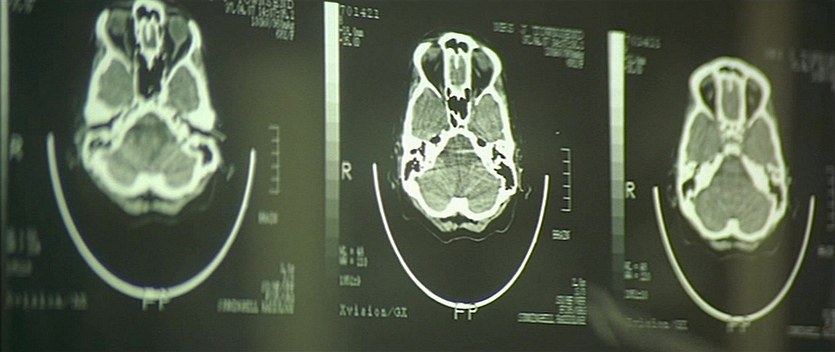

Who Am I? (1998)

Name: Who.Am.I.1998_04880

Source: Blu-ray 1080p